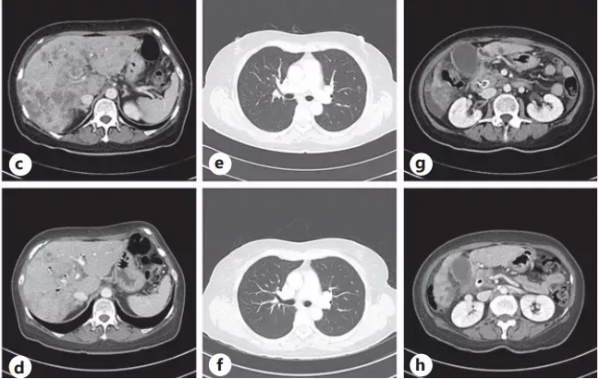

圖2. (a)脂質體伊立替康治療前,胰腺癌的原發灶和多發性肝轉移。(b)脂質體伊立替康五個月後,原發灶體積縮小,肝轉移消失

停藥兩個月後,患者病情加重,確診為廣泛肝轉移(圖2 c-e),經多方考量,決定重新應用NAPOLI方案。治療再次有效,共持續了7個月(2020年7月–2021年1月),CT 顯示胰腺腫物減小,轉移病灶均有所改善。

圖2.(c-e)在重新使用脂質體伊立替康之前,廣泛的多發性肝轉移、腹水、原發腫塊的大小增加和肺轉移。(f-h)再次使用脂質體伊立替康後6周,改善多器官轉移並減少原發病灶。